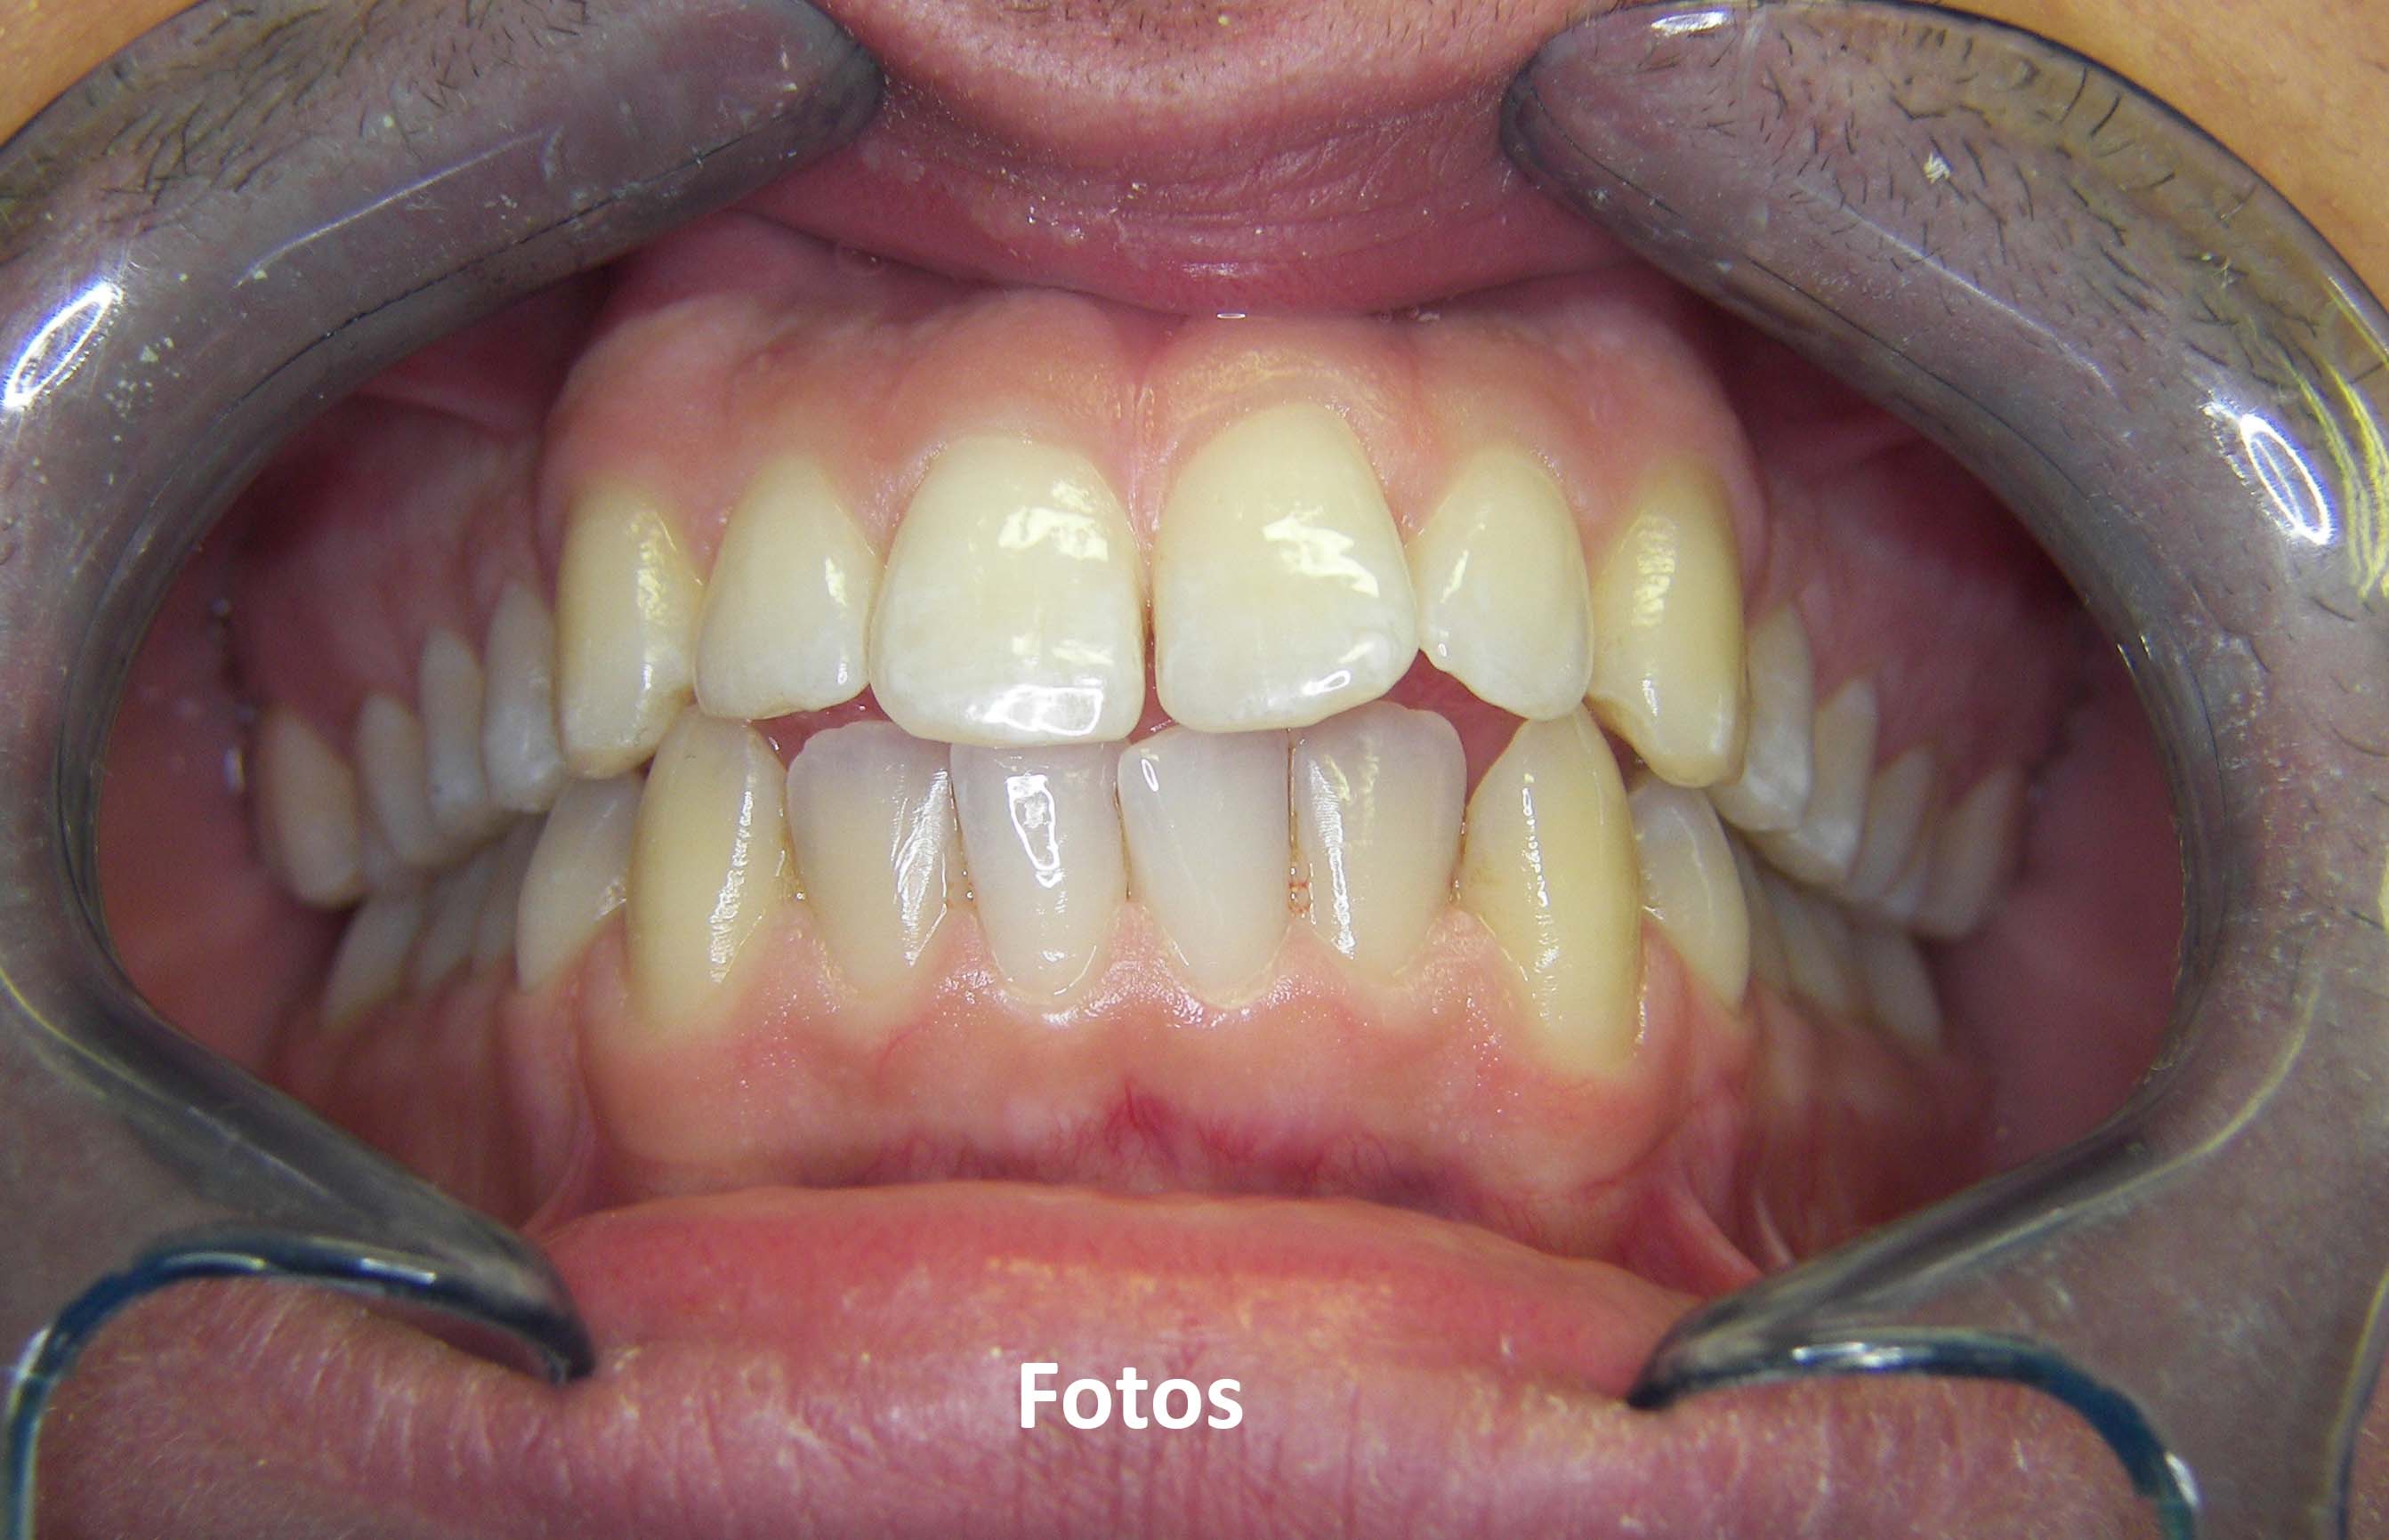

• Photos

After all information is taken a diagnosis is done and a treatment plan is discussed and decided in the patient´s best interest.